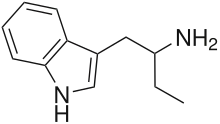

αET | 1-(1H-indol-3-yl)butan-2-amine | 2235-90-7 |

|